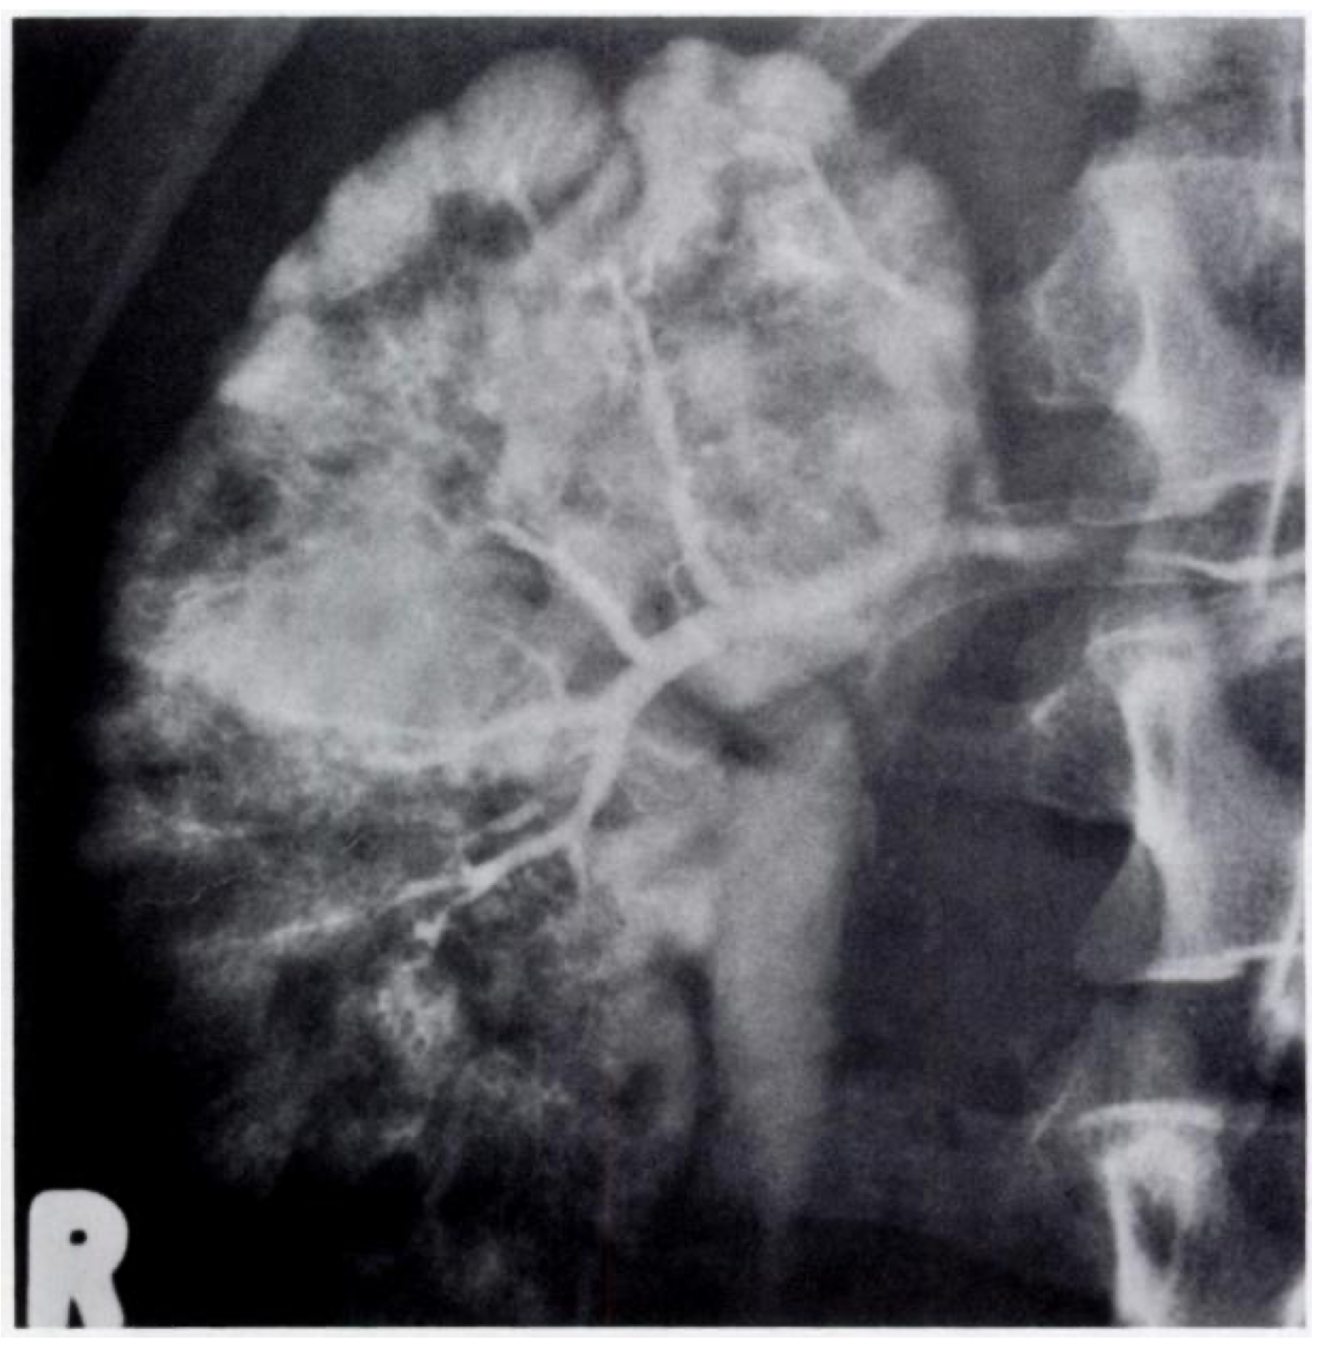

Figure 5B

This is a late phase from a selective renal arteniogram in the same patient; it demonstrates occlusion of multiple peripheral vessels with cortical irregu- lanity.